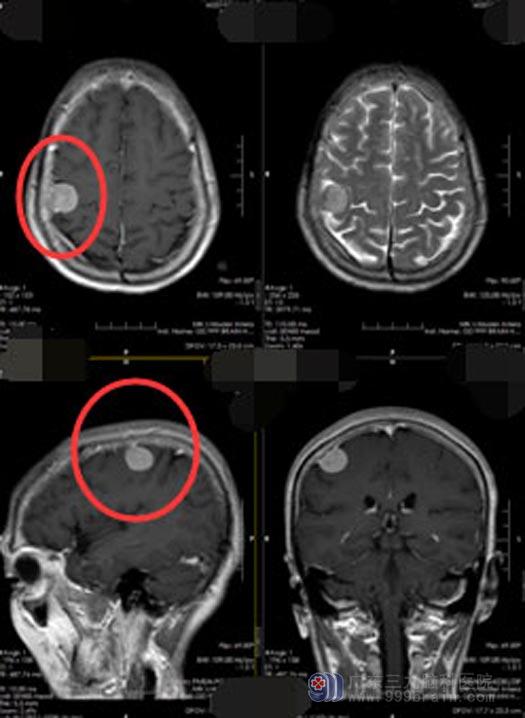

直到今年11月23日,她在当地医院进行头颅CT检查,才发现 “右侧额顶叶占位,考虑脑膜瘤可能性大”,这让关阿姨一家人大吃一惊,这头痛了40多年的原因竟然是因为脑袋里长了肿瘤。

12月4日,神经外五科手术团队为关阿姨实施了“右顶部脑膜瘤切除术”,手术利用显微镜仔细分离肿瘤与软脑膜,完整切除肿瘤,并去除部分受到肿瘤侵犯的硬脑膜,手术过程非常顺利。